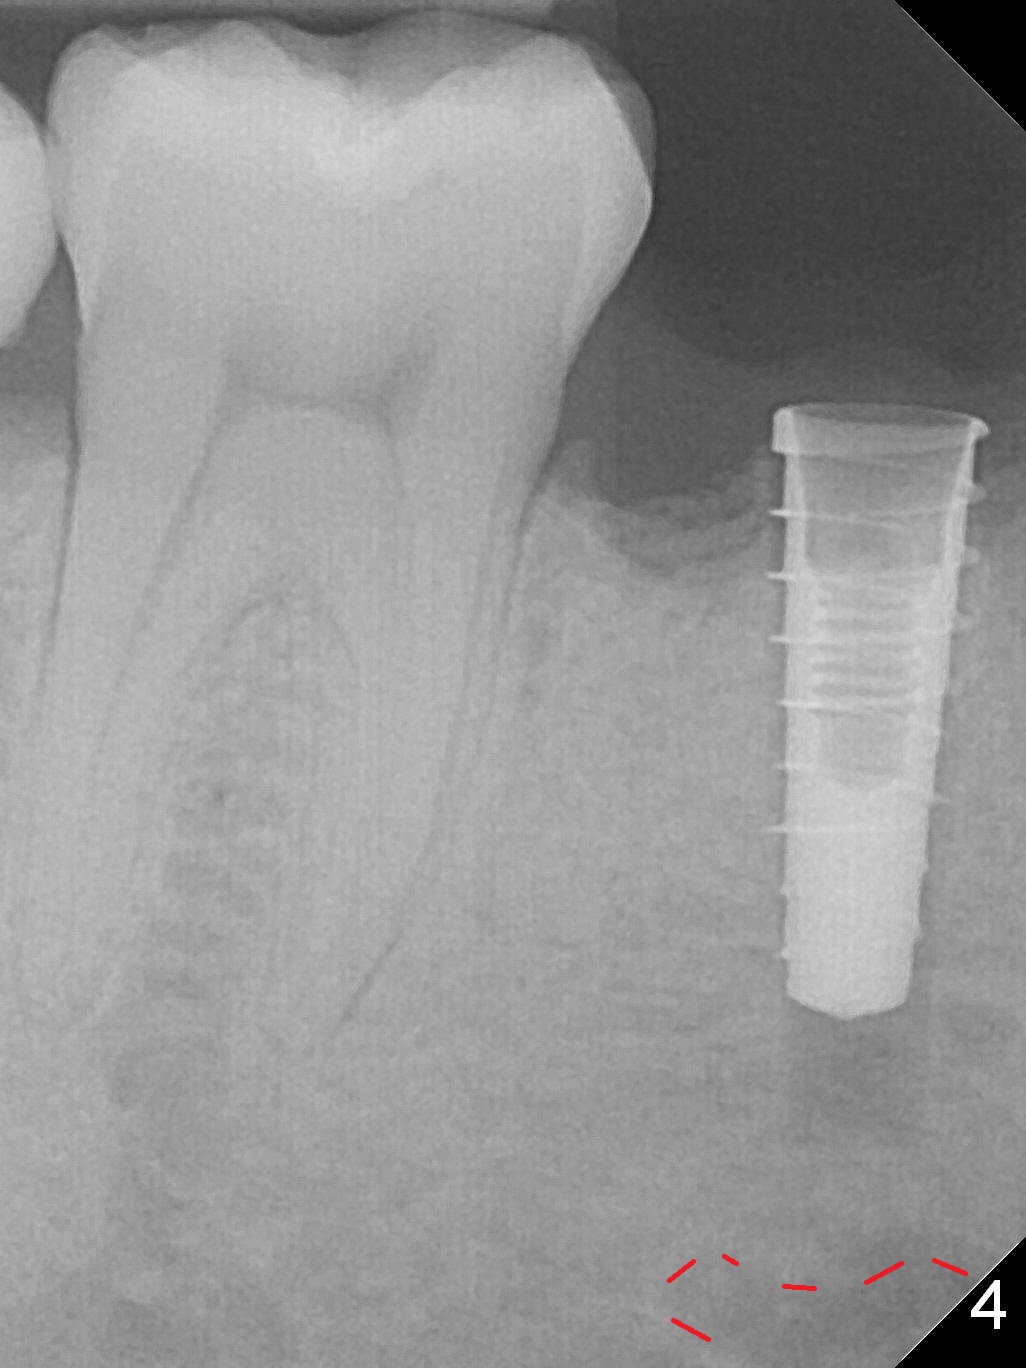

The lower 2nd primary molar has buccal furca lesion (Fig.1 *) with the thin buccal plate (Fig.2). Osteotomy is initiated in the sloped septum (Fig.3). After use of Magic Drill (MD) 3.3 mm for 13 mm and MD 3.8 mm for 11 mm, placement of a 4x11 mm IBS implant meets resistance because of the dense bone (Fig.4-6, red dashed line: Mental Loop) with final insertion torque >50 Ncm. After placement of a 6x4(3) mm abutment and autogenous bone in the remaining shallow sockets (Fig.6), a provisional is fabricated (Fig.7). Finally periodontal dressing is applied. Impression is taken 3 months postop (Fig.8). Buccal infection develops 2 weeks post cementation (Fig.9). When the crown/abutment is removed, there is no residual cement. The implant threads can be felt through the fistula. After soft tissue debridement and copious irrigation, Arestin is placed in the fistula. The latter disappears 15 days post debridement. The patient feels better and moves out of state. It appears that early periimplantitis develops because of the preexisting buccal furca lesion and failure to place the implant deep. The implant will be placed deep after loosening a little (since there is apical space (Fig.8 white line)) or removed, truncated at the apex and placed lower than the buccal crest.